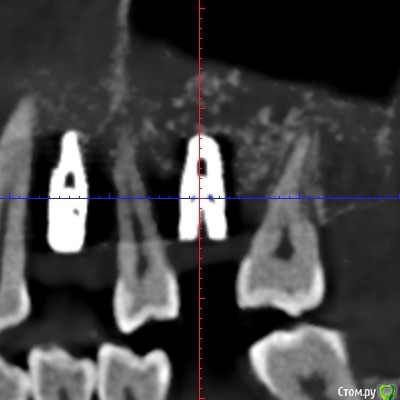

Irina_S Опубликовано 6 января, 2018 Поделиться Опубликовано 6 января, 2018 Здравствуйте, уважаемые спеицалисты! С наступившим вас Новым годом!!! В конце августа были установлены три имплантата Xive - 36, 46, 47. Одновременно с установкой выпиливалась кость и прикручивалась винтиками в те места, где по мнению хирурга её не хватало. В середине октября сквозь десну с язычной стороны стали просматриваться верхушки имплантатов 36 и 46. Во время периодических осмотров врач говорил, что всё в порядке.В декабре пришло время установки формирователей десны. Установивший имплантаты хирург стал работать в другой клинике. Он пригласил на осмотр, сказал, что надо будет добавить десну в области 36 и 46, взяв кусочки с нёба, а с самими имплантатами всё хорошо, можно одновременно с пластикой десны ставить формирователи и через 2-3 недели отправляться к ортопеду.Следуя логике сохранения гарантии на установку имплантатов, которую даёт не врач, а клиника, я пошла к другому хирургу в ту клинику, где устанавливались имплантаты. Он посмотрел на выступающие верзушки имплантатов, причём 36 успел к этому времени уже прорвать десну. Посмотрел КТ и сказал, что предварительно видит проблемы и помимо пластики десны может понадобиться переустановка имплантатов. Самый проблемный, по его мнению, 46, а 36 - под вопросом. Сказал, что окончательное решение можно будет принять только после разрезания десны, чтобы увидеть фактическую ситуацию. Причём переустановка - по гарантии, и она будет делаться сразу - выкручивается старый имплантат и ставится новый, тоньше (3,8мм вместо 4,5мм) и длиннее. Соответственно, в этом случае снова ждать 3-4 месяца, и только после этого ставить формирователи. Присутствовавший на консультации ортопед был полностью с ним согласен и сказал, что на имплантаты в таком состоянии, как он их видит на КТ, он коронки ставить не будет. Аргументировалось тем, что кости в принципе достаточно, но имплантаты надо было устанавливать глубже, а так, как сейчас, они протянут максимум 3-4 года, а потом расшатаются и выпадут. Клиника даёт гарантию 10 лет, поэтому они считают, что нужно хорошо установить изначально.На месяц раньше ставились имплантаты в верхнюю челюсть, с ними всё хорошо. Но, рассматривая проекции КТ, я вижу обширные тёмные области в районе всех имплантатов как дефект засветки при формировании КТ. В связи с чем вопрос: может ли картина на КТ с отсутствием видимой костной ткани происходить из-за самого оборудования, на котором делается КТ, и не совсем соответствовать действительности? Иначе, есть ли шанс, что при вскрытии десны окажется, что с расположением импллантатов всё в порядке (как и уверяет "сбежавший" их этой клиники хирург), а альтернативное мнение связано в некотором роде с желанием опозорить уволившегося сотрудника и удержать пациента у себя, ведь потом предстоит большая ортопедическая работа? И ещё один вопрос: чего мог категорически не принимать ортопед, говоря, что в подобных случаях он всегда отправляет к хирургу, если заведомо было известно, что недостающая десна в любом случае будет наращиваться?С имплантатом 47 ситуация, вроде бы, не такая критическая. Это на самом деле так? Ссылка на комментарий

колесников Опубликовано 6 января, 2018 Поделиться Опубликовано 6 января, 2018 С десной однозначно предстоит поработать. Импланты расположены несколько язычно,что может быть проблематично. Ссылка на комментарий

колесников Опубликовано 6 января, 2018 Поделиться Опубликовано 6 января, 2018 Сколько врачей,столько и клинических подходов. Я бы переустановил нижние импланты заменив ксайв на Штрауман тл, плюс увеличил объём мягких тканей по гребню.Это ,как говорится ,обойтись малой кровью с благоприятным прогнозом. Если оставлять этот ксайв,то только пластики десны не достаточно,придётся перекрывать их костным материалом с мембраной и позднее Увеличить объём мягких тканей. Все бы ничего,но меня смущает язычное положение платформ имплантов и их уровень относительно соседних зубов. Это лично моё мнение,оно может отличаться от мнений коллег. Ссылка на комментарий